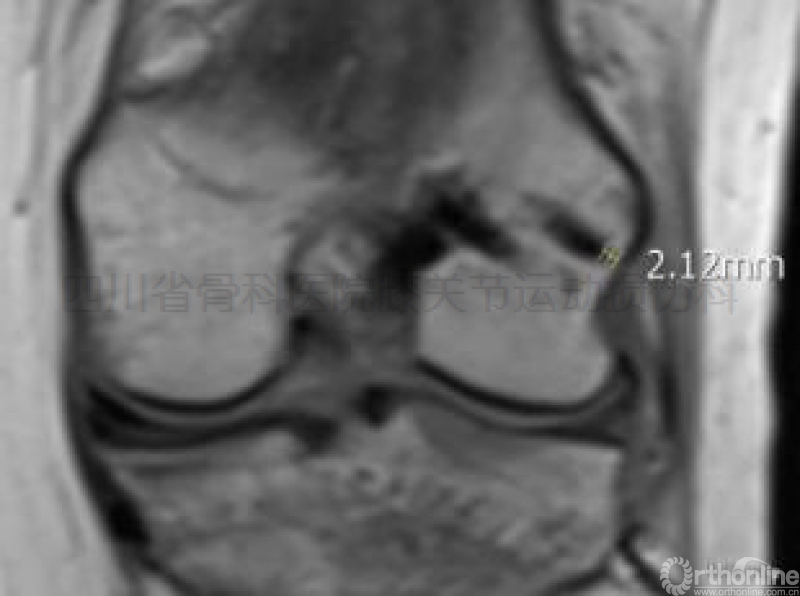

①击入点导针和鞘管仅穿过股四头肌内侧头,击入点与内侧髌股韧带的最短距离大于20mm(图示四),

图示四经前内入口安全区逆向横穿于股骨内髁击入区所见:a、b点为RigidFix

鞘管击入点,c点为内侧髌股韧带股骨止点。击入点与该韧带之最短距离>20mm。

击入点与内侧副韧带股骨止点的最短距离大于25mm(图示五);

图示五经前内入口安全区逆向横穿于股骨内髁击入区所见:a、b点为RigidFix

鞘管击入点,c点为内侧副韧带股骨止点。击入点与该韧带之最短距离>25mm。